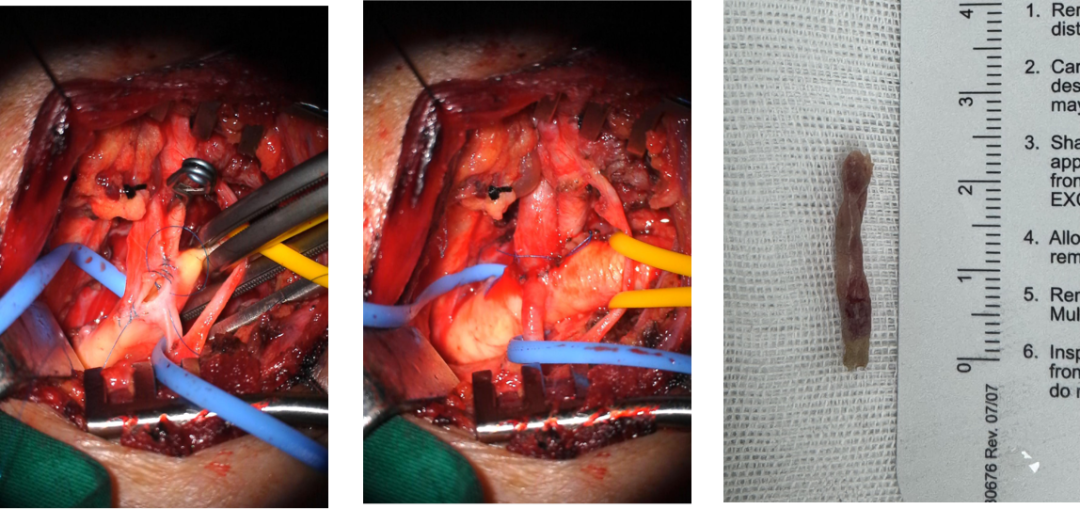

M,60,左侧小脑梗死,左椎动脉V1-V2段长段闭塞

椎动脉外翻剥脱、椎动脉-锁骨下动脉端侧吻合

椎动脉-锁骨下动脉端侧吻合

介入开通